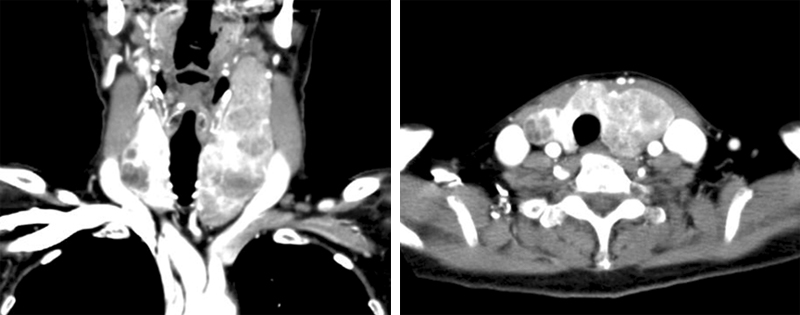

Urk-CT-thyroid.jpg

甲状腺CT:甲状腺左葉から峡部腫大, 内部に不均一に染まる低濃度腫瘤あり。

頚部気管が右に偏位。右葉にも複数の低濃度結節あり。頚部リンパ節腫大なし.

PET-CT他, 画像診断では甲状腺以外にリンパ節および節外臓器病変は認められず原発と考えられる。